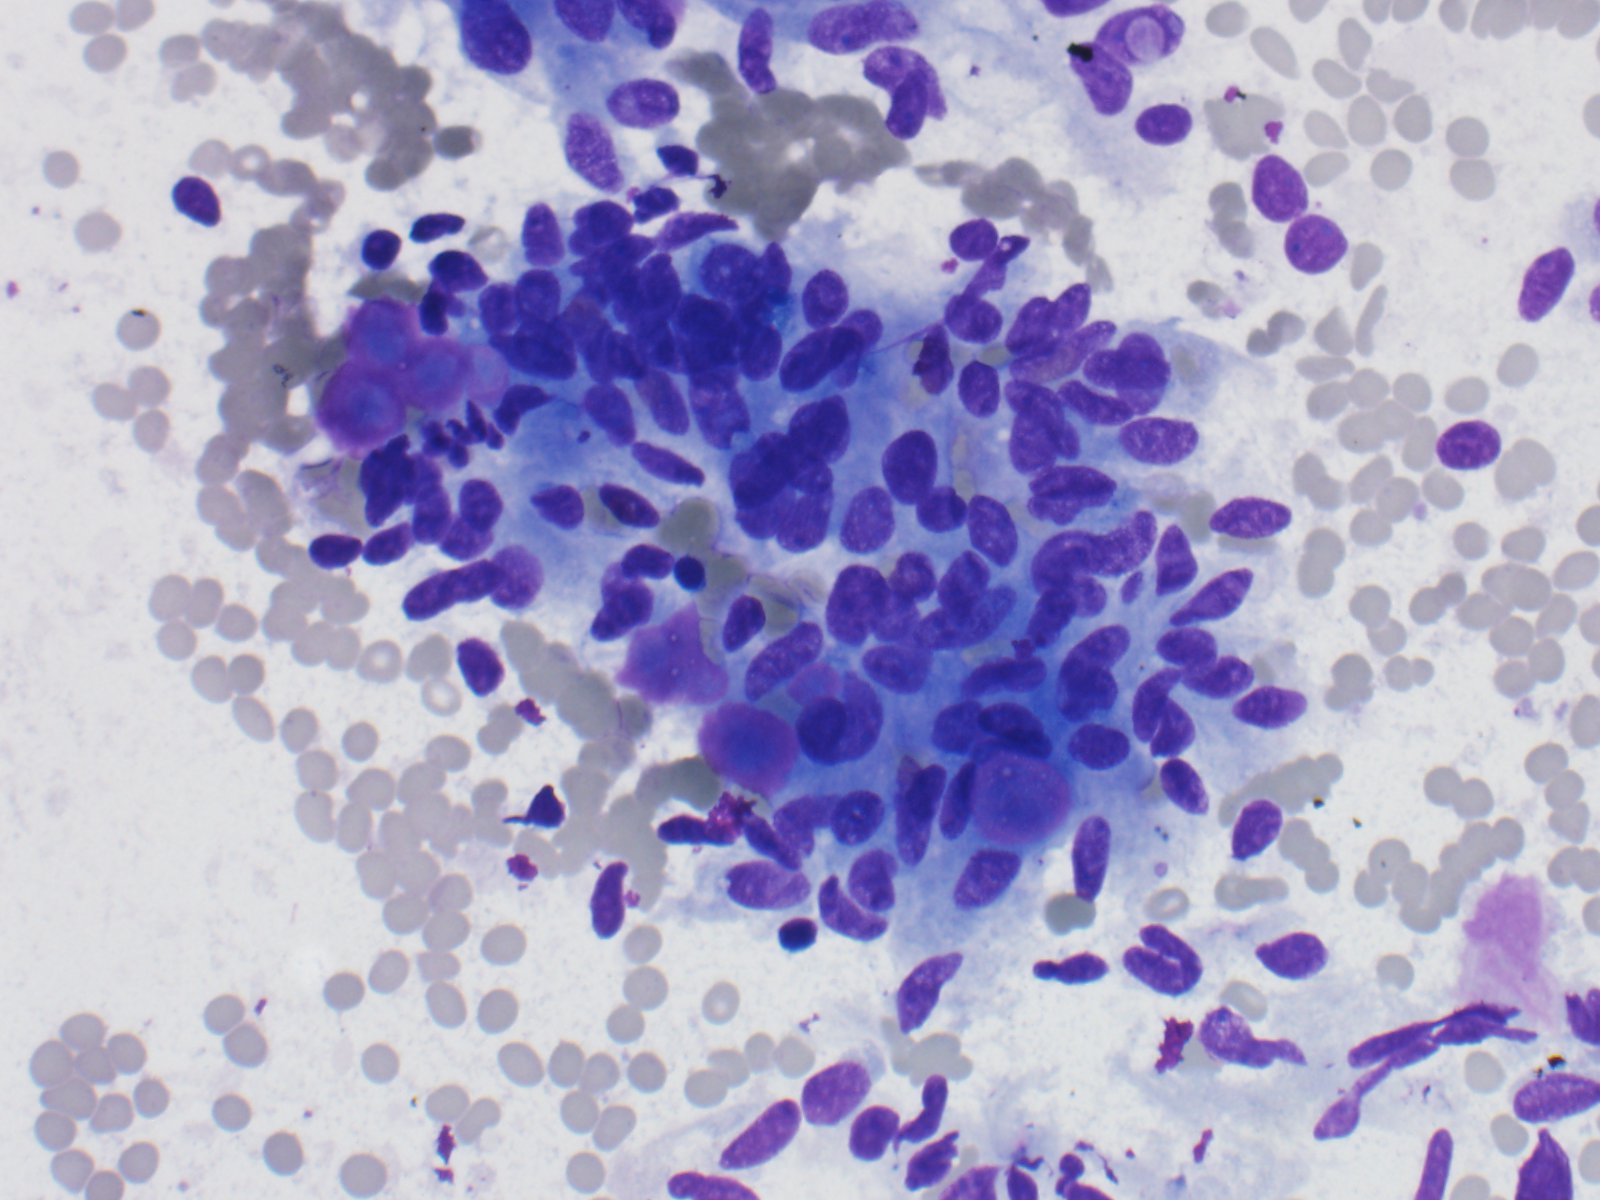

The specimen consists of variably sized fragments of cells with elongated/spindled nuclei, intranuclear inclusions, moderate amounts of cytoplasm, and some eosinophilic amorphous material.

An original diagnosis of medullary carcinoma was rendered. There was insufficient material for cellblock, therefore the patient underwent serologic testing. Calcitonin and CEA levels were normal, which prompted a conversation with the endocrine surgeon to determine best course of treatment for the patient. An Afirma vial was available, and was sent for molecular analysis, which showed a PAX8/GLIS3 rearrangement. Taken together with the morphology, the serologic findings and the molecular result, the final diagnosis was hyalinizing trabecular tumor (in this case, mimicking medullary thyroid carcinoma). Lobectomy was subsequently performed, which confirmed the original cytologic diagnosis.

HTT of the thyroid is a rare follicular derived neoplasm that occurs more commonly in middle-aged euthyroid females, incidentally found. They have a characteristic rearrangement of GLIS and have a favorable prognosis. Cytologically, the cells resemble papillary thyroid carcinoma, medullary thyroid carcinoma and non-invasive follicular thyroid neoplasm with papillary-like nuclear features. On surgical pathology, HTT exhibits a prominent trabecular pattern, abundant intratrabecular hyalinized stroma and characteristic nuclear features of papillary carcinoma.